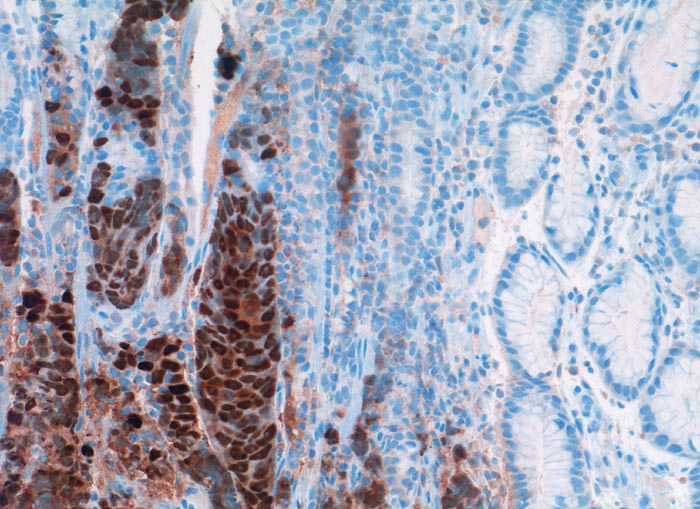

Östrogenrezeptor

Anfärbung:

Zellkern. Zytoplasmafärbung ist unspezifisch.

Reaktion im Normalgewebe:

Epithel und Stromazellen von Vulva und Vagina. Endometrium. Mammaepithelien.